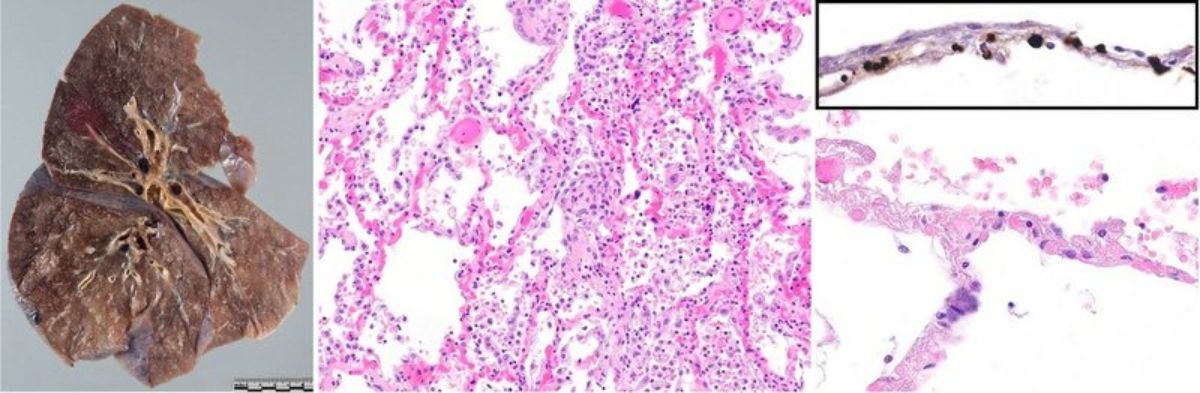

Autopsy findings from this cohort provided initial broad evidence of a rather characteristic morphologic pattern of lung changes in COVID-19 with deep-red, slightly nodular, hyperemic and very heavy lungs with prominent diffuse alveolar damage, and, most importantly, microvascular thrombosis and capillary congestion (Figure 1).

Figure 1. Left: Gross appearance of a COVID-19 lung. Middle: Diffuse alveolar damage with hyaline membranes in a patient with lethal COVID-19 with prominent capillary stasis. Right: Upon higher magnification, thrombotic occlusion can be observed in alveolar capillaries. Inset: Immunohistochemical staining for fibrin reveals occlusion of alveolar capillaries by microthrombi.